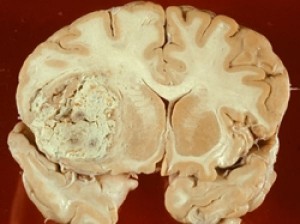

Szövettan tumorok bemutatott asrotsitami fibrilláris típusú, innen a név a tumor. A mikroszkópos vizsgálat az összes sejtek nem különböznek a normális, nem kell jelei celluláris atypia és kóros mitózis. Ezek zárt egyetlen konglomerátum, homogén szerkezet nélkül nekrotikus változásokat és a megjelenése érstruktúrák. Az egyetlen kivétel a nagy tumorcsomók, amelyek miatt az eltérés a kínálat és megfelelőségét vérellátás elhalt. Ennek eredményeként, egy ciszta fibrilláris asztrocitóma kiformált, töltött véres vagy piszkos-barna folyadék.